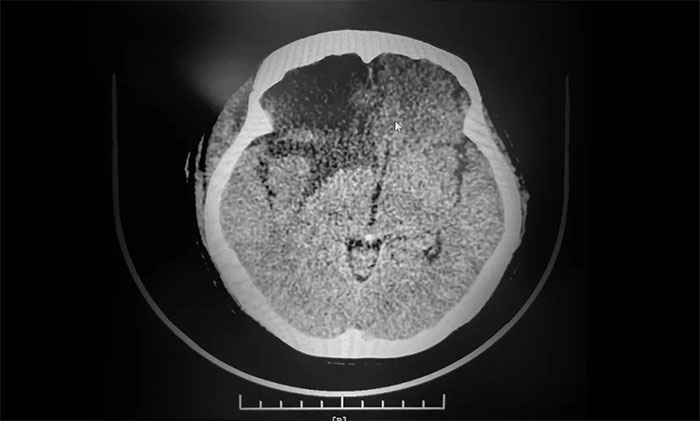

▲ 术后影像,肿瘤已切除